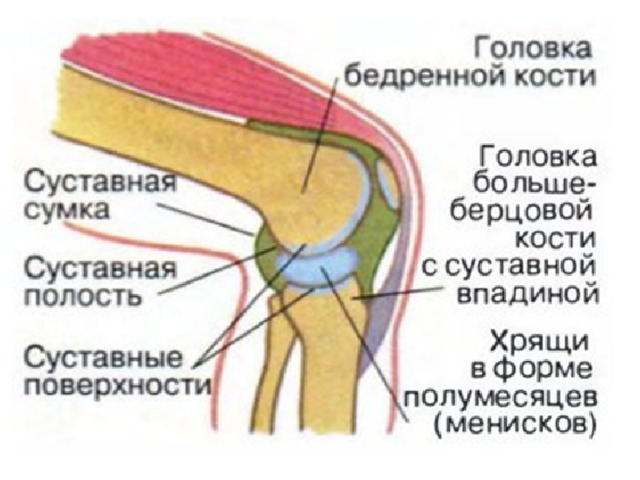

Рисунки Суставов: Анатомические Иллюстрации